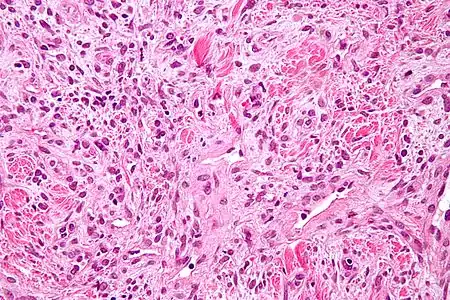

Histologie

Les tumeurs fibreuses solitaires sont constituées de cellules mésenchymateuses, de différenciation fibroblastique[6]. Elles sont ovoïdes ou fusiformes. Leur cytoplasme est riche en collagène[3]. L'architecture tissulaire est hétérogène, supportée par un tissu conjonctif collagénique et alterne entre des zones bien fournies en cellules et des zones plus pauvres, où l'espace intercellulaire est plus riche en acide hyaluronique[3].

L'immunohistochimie retrouve l'antigène CD34 dans 80 % des cas[30], ce qui permet de différencier les tumeurs fibreuses solitaires des mésothéliomes[3]. Les tumeurs expriment également la vimentine, mais aucune des cytokératines[30].

Il existe quelques variantes histologiques. Les tumeurs fibreuses solitaires dites « anaplasiques » ou « dédifférenciées » sont de moins bon pronostic et peuvent prendre l'aspect d'un sarcome pléomorphe. Les variantes myxoïdes et lipidiques ne modifient en revanche pas le pronostic[48]. Les différents types de fusion entre les gènes NAB2 et STAT6 pourraient être à l'origine de ces variantes histologiques[49].

La proportion de tumeurs fibreuses solitaires malignes varie selon les séries de 6 %[24] à 23 %[1], voire un tiers des patients[13],[29]. Lors de l'analyse anatomo-pathologique, certaines tumeurs fibreuses solitaires présentent en effet des caractéristiques de tumeur maligne. La première définition des critères de malignité dans ces tumeurs a été réalisée par England en 1989[13]. Il identifie ainsi[22] une concentration cellulaire importante, une activité mitotique élevée, le pléomorphisme (aspect variable des cellules), et la présence d'hémorragie et de nécrose intra-tumorales. La perte d'expression de CD34 est fréquente[3]. Cependant, ces caractéristiques histologiques d'agressivité ne sont pas toujours corrélées à un plus mauvais pronostic[50], et environ 2 %[51] des formes bénignes évoluent de manière agressive[1].